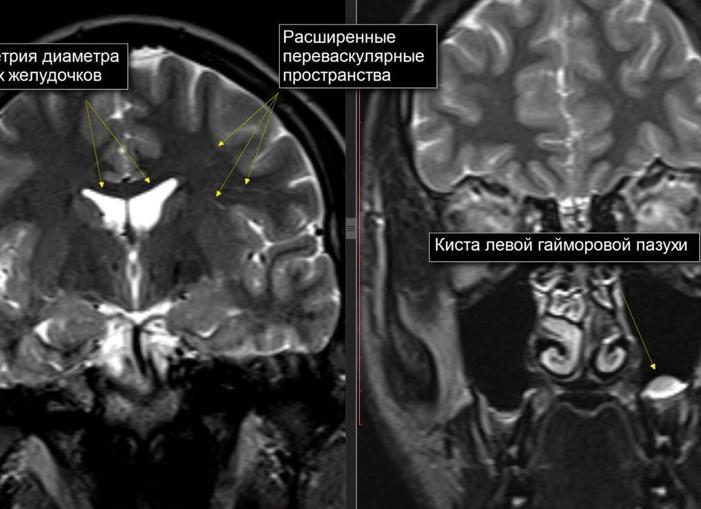

Расширение боковых желудочков диагностируется исключительно с помощью инструментальных методов. В необходимый объем процедур входят:

• нейровизуализация (КТ, МРТ);

При этом только нейровизуализация позволяет точно оценить ширину и размеры вентрикулярных полостей от передних до задних рогов, а также проанализировать состояние желудочковой системы в целом. Остальные методы диагностики являются вспомогательными и используются в качестве дополнительных процедур.